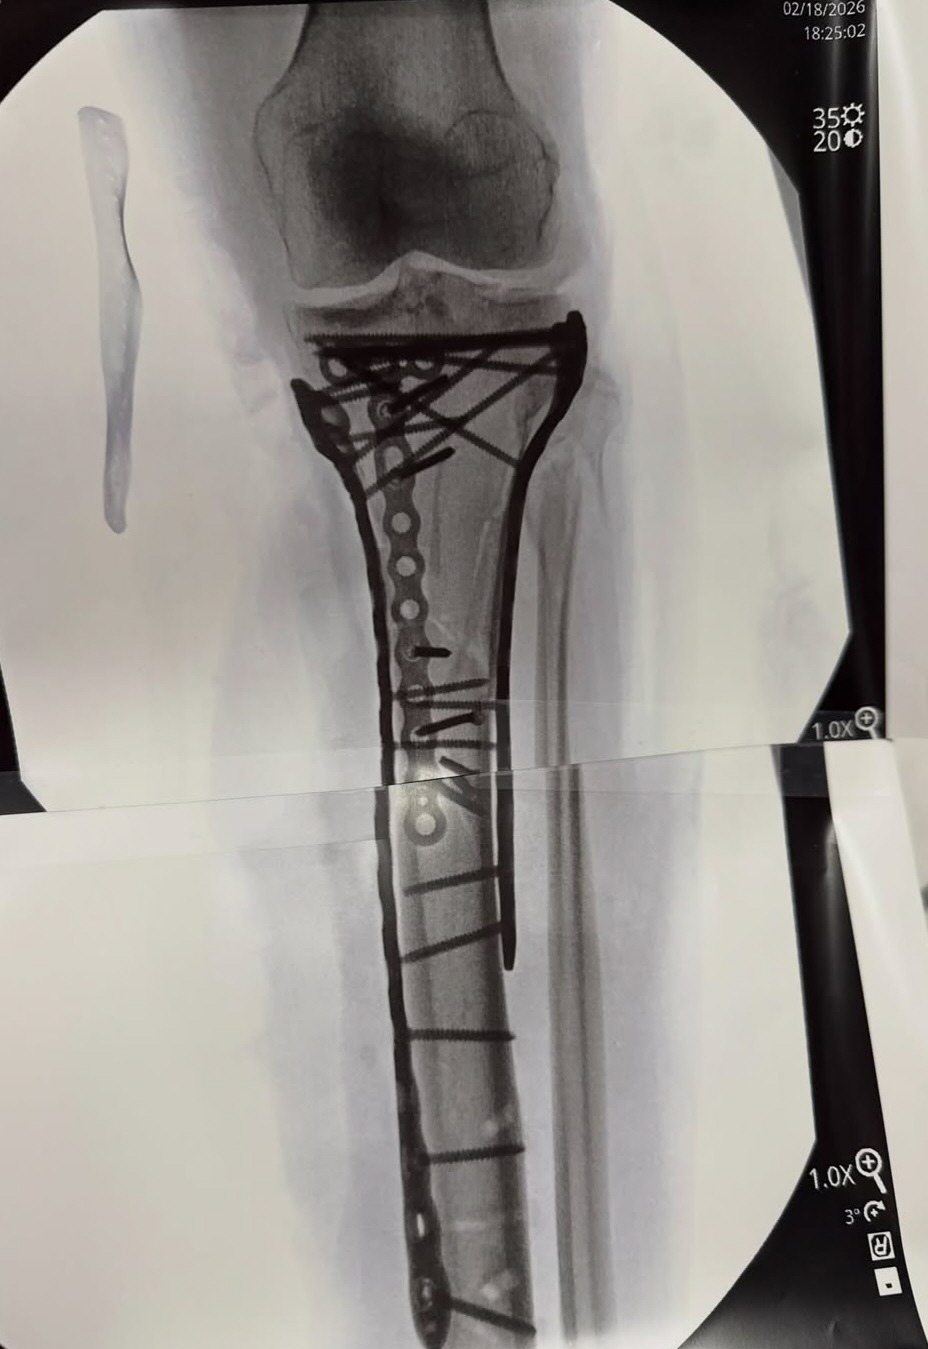

그는 금속판과 나사가 박힌 엑스레이 사진도 공개했다. 본은 올림픽에서 총 3개의 메달을 따냈다. 2010년 밴쿠버 대회에서 활강 금메달, 슈퍼대회전에서 동메달, 2018년 평창 대회에선 활강 동메달을 목에 걸었다. 2014년 소치 대회는 부상으로 불참했다.

본은 무려 5차례나 대수술을 받았다. 그는 최근 치료 과정을 담은 영상과 글을 올렸다. 본은 "항상 모든 일에는 이유가 있다고 말하지만, 만약 내가 전방십자인대 파열 부상을 당하지 않았더라며, 톰 해켓 박사님이 내 곁에 없었을 거고, 내 다리를 구할 수도 없었을 거다. 해켓 박사님이 내 목숨을 구해 주셨다. 다리를 절단하지 않도록 해주셨다"며 "오른쪽 발목도 부러져서 당분간 휠체어를 타야 할 것 같다. 조만간 목발을 짚고 걸을 수 있기를 바라지만, 두고 봐야한다. 하지만 재활에 전념해서 최대한 빨리 회복할 수 있도록 노력할 거다. 늘 그랬듯이 한 단계씩 차근차근 나아갈 거다"라고 밝혔다.